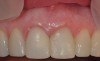

Fig 9. Completed crowns at 5 years, front view. Implant No. 9 was screw-retained (periodontist: Robert A. Levine, DDS; restorative dentist: Zola Makrauer, DMD).

Figure 9

Fig 10. Completed crowns at 5 years, angled view. Note the convex contours facial to implant No. 9 attributed to the connective tissue grafting.

Figure 10

Fig 11. Patient smile at 5 years.

Figure 11

Figure 8 shows the provisionalization of No. 8 at 6 weeks postoperatively and a screw-retained provisional restoration on No. 9 to develop the subgingival transitional zone (key Nos. 8 through 10). The transitional zone will be duplicated using the custom impression coping technique. Figure 9 and Figure 10 depict the completed crowns at 5 years; implant No. 9 was screw-retained (key No. 10). In Figure 10 note the convex contours facial to implant No. 9 that are attributed to the connective tissue grafting as part of the surgical protocol creating biotype conversion from a thick to a thicker biotype. Figure 11 through Figure 13 show 5-year postoperative patient smile, periapical x-ray, and CBCT, respectively.